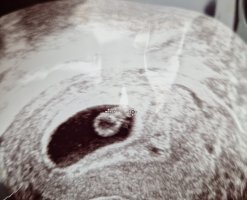

Hurra! Gratulerer så mye! Skjønner godt du er nervøs, men håper det holder hele veien denne gangenVis vedlegget 423276

Skal litt ekstra til for å senke skuldrene når man har opplevd å miste Hurra!Vis vedlegget 423276

Gratulerer så myeVis vedlegget 428039

Her ser det heldigvis ut som det går riktig vei så langt. Jeg hadde ultralyd 6+1 og 8+1 privat. På den første var jeg først overlykkelig over å se at det var «noe» der, og ikke tomt. Men ble også litt stressa fordi det er vanskelig å måle så tidlig, ble målt to dager kortere og gyn sa det var hjerteaktivitet (så hang meg opp i at det kanskje ikke var helt på plass). Så tryggheten fra den 6+1 var kortvarig. Skulle jeg gjort det igjen ville jeg kanskje ventet til 6+4-6 for å ikke bli stresset av at det er for tidlig til å se ordentlig.

8+1 var veldig betryggende, der så alt normalt ut og jeg ble målt til 8+0. Det er bare noen dager siden, så nå går jeg å vurderer om jeg klarer å vente i fire uker til toul eller om vi må kjøpe oss enda litt mer trygghet